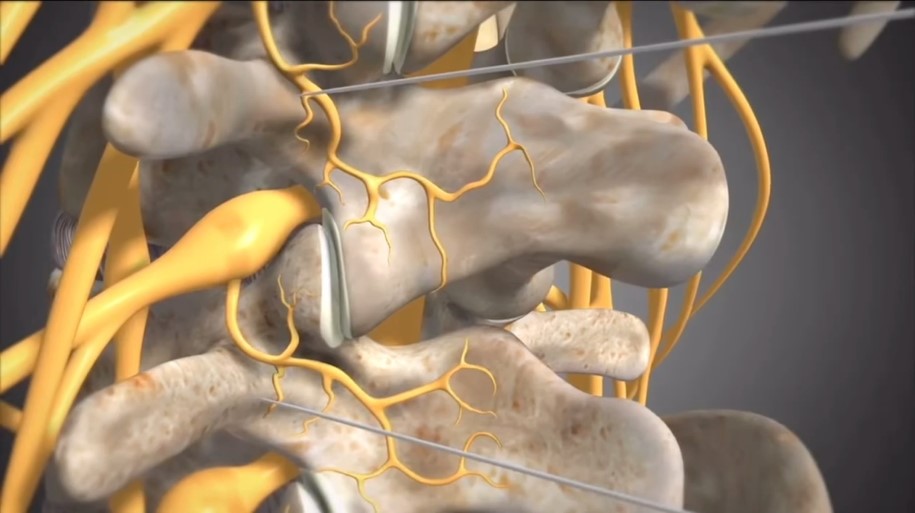

Остеоартрит фасеточных суставов: медицинские снимки и схемы